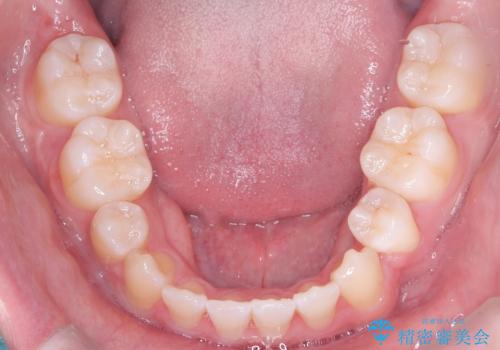

- 前歯のガタガタや正中の不整を改善するために、右上4、左上4、左下4を抜歯し、矯正治療を行いました。この治療により、見た目だけでなく、咬合のバランスも改善され、患者様の口腔内の健康が向上しました。

審美ワイヤー装置は、見た目を重視した矯正治療において非常に有効な選択肢です。患者様のニーズに応じた治療が可能で、美しい歯並びを目指すことができます。